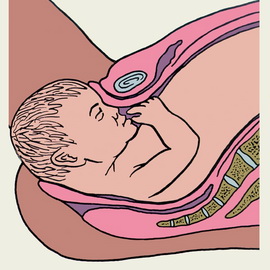

5. Розгинання голівки, він відповідає моменту врізання і прорізування головки тазового дна (вона вперше з'являється із статевої щілини).

6. Внутрішній поворот тулуба і зовнішній поворот голівки. Народжена голівка повертається потилицею до правого або лівого (в залежності від позиції) стегна матері.

7. Народження тулуба і всього тіла плоду. Спочатку під лобковим симфізом з'являється переднє плічко. Тулуб згинається в грудному відділі і відбувається народження заднього плічка і ручки, після чого народжується переднє плічко і все тіло.

Пологи: період вигнання плода

На початку другого періоду пологів породіллю переводять у пологову кімнату. Її укладають на спеціальне ліжко в положенні лежачи на спині, головний кінець ліжка піднімають, ноги максимально розводять, згинають в колінах і тазостегнових суглобах. З метою знезараження зовнішні статеві органи обробляють розчином йоду або перманганату калію.

Потуги піддаються регулюванню - ослаблення або посилення. У цей період важливо правильно дихати і направляти свої зусилля. Після глибокого вдиху і затримки дихання необхідно упертися ногами і напружуючи стегна тужитися діафрагмою і животом. Не потрібно направляти свої зусилля на-віч. У цей період важливо зосередити всі сили на роботі необхідних м'язів. Після потуги важливо максимально розслабитися, щоб набратися сил для наступної потуги, і так до народження дитини.

Рот і ніс немовляти очищають від слизу, іноді його можуть потримати вниз головою, щоб видалити слиз з легких. Новонароджений робить свій перший вдих і видає свій перший крик: «Я народився!» Пуповину перерізають після закінчення пульсації пуповини судин. Весь цей час дитина лежить на животі або грудей матері, проводять його перше прикладання до грудей. Після перетину пуповини малюка передають неонатолога і медичній сестрі дитячого відділення. Кожен новонароджений на перших хвилинах життя оцінюється за шкалою Апгар.